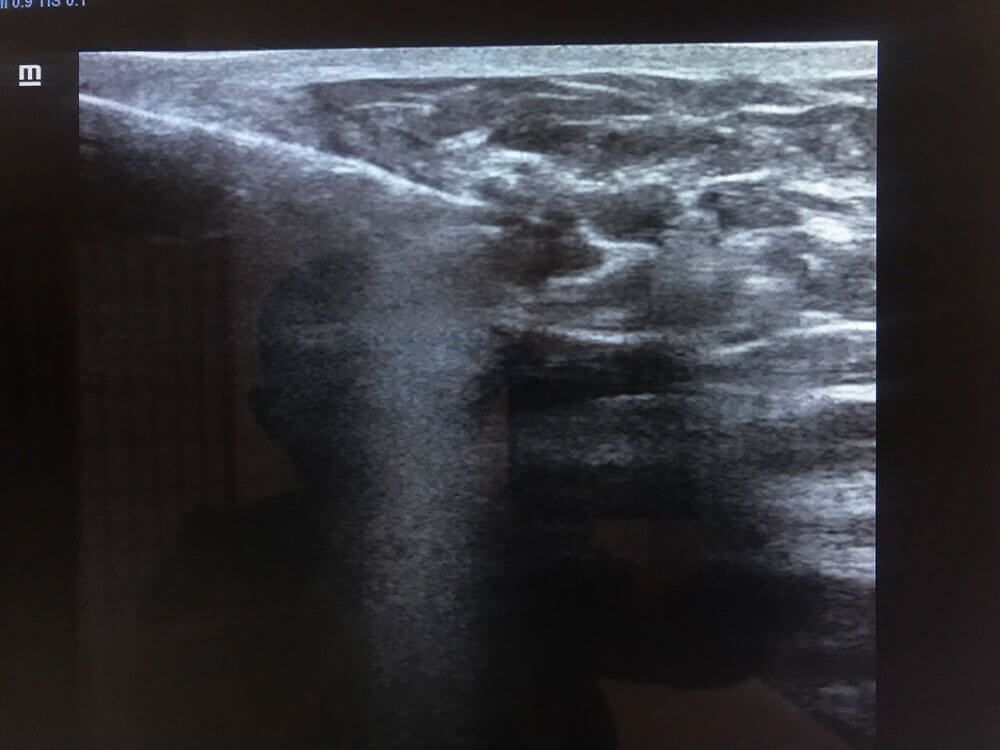

Realizamos

ultrasonidos

convencionales, gestacionales, pediátricos, especializados, entre otros. También aplicamos estudios con